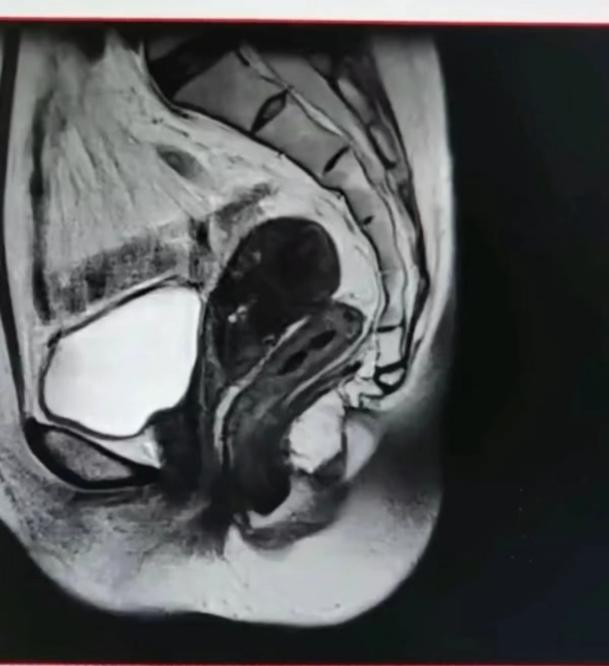

门诊查白带、HPV、TCT结果未见异常。2024-5-8宫腔镜下诊刮内膜病检示:子宫内膜不典型增生伴局部癌变。免疫组化:PTEN(+),PAX-2(-),MLHI(+),P53(突变型表达),Ki67(热点区约75%+),PMS2(+),MSH2(+),MSH6(+),ER(90%强+),PR(80%中等-强+),CD10(局部问质-),P16(部分+),CEA(-)。入院后完善各项检查,盆腔增强MRI示:子宫后位,前壁结合带信号不均匀,局部内膜凹凸不平,浸润深度>1/2肌层,子宫浆膜层完整,子宫多发肌瘤,盆腔少量积液,未见淋巴结肿大。上、下腹、盆腔增强CT,胸部CT未见明显异常、血常规、血脂、肝肾功能、生化、凝血、心电图、肿瘤标志物等结果均未见明显异常。

盆腔MRI: